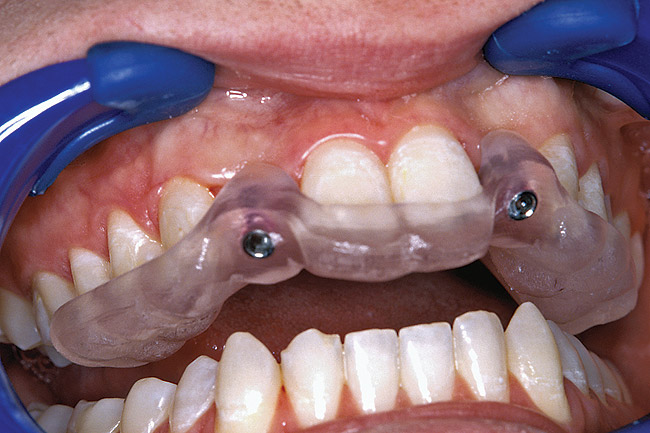

Figure 31  VIRTUAL PLANNING AND SURGERY A surgical template was derived from the final treatment plan created in the software, which facilitated the drilling sequence and precise location of placement.

Figure 31

Figure 32  VIRTUAL PLANNING AND SURGERY A surgical template was derived from the final treatment plan created in the software, which facilitated the drilling sequence and precise location of placement.

Figure 32